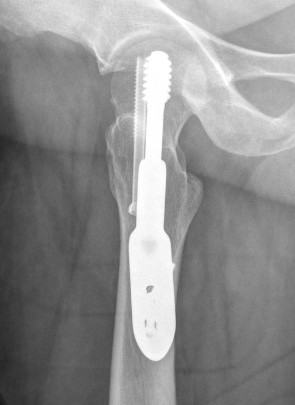

Synthes FNS (Femoral neck system)

Technique

Synthes FNS surgical technique guide